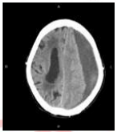

6. 女性 86 歲,近日來嗜睡,今早叫不醒,被送至急診室。家屬表示約 3 週前曾經跌倒, 頭部雖有撞到傢俱,但無明顯外傷。目前腦部電腦斷層檢查結果如下圖,病人最可能的診斷為何?(A) 腦內出血(B) 硬腦膜上血腫(C) 硬腦膜下血腫(D) 蜘蛛網膜下腔出血